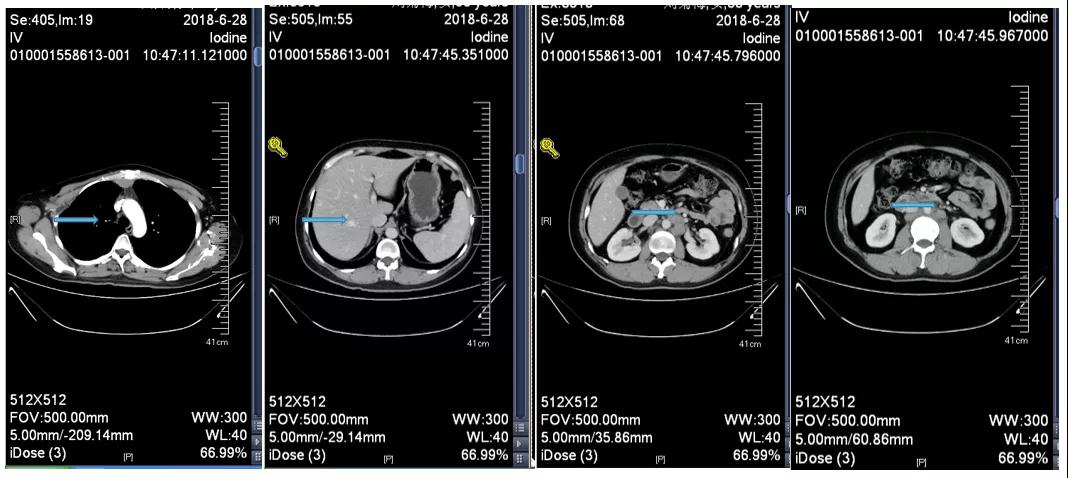

胸腹部增强CT示(2018-6-28):胸骨后占位,肝内异常强化灶,腹膜后肿大淋巴结。

诊断:右乳浸润性癌(rT2N3M1 IV期 HER2过表达型);卵巢转移瘤切除术后;腹膜后淋巴结转移;纵隔淋巴结转移;肝转移。

靶病灶:腹主动脉左侧和下腔静脉右侧淋巴结

非靶病灶:肝左叶、肝右前叶下段;纵膈胸骨后淋巴结节;前上纵膈淋巴结;腹膜后小淋巴结

影像学评估-肝脏:

影像学评估-腹膜后淋巴结: